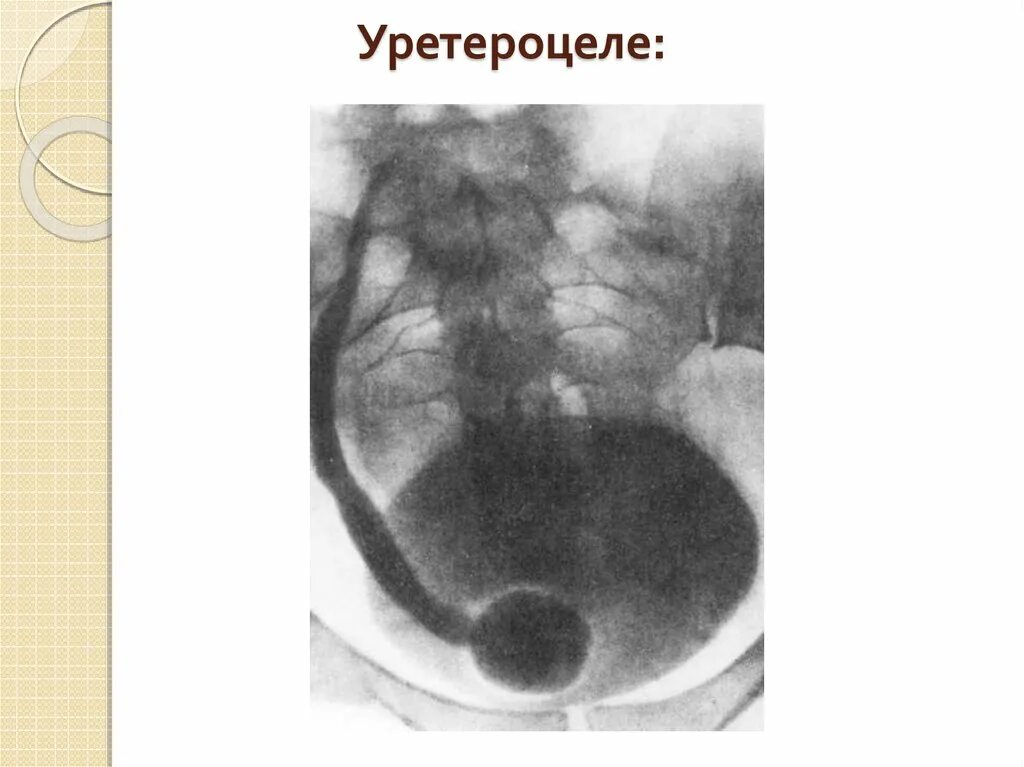

Дивертикул мочевого пузыря что это такое